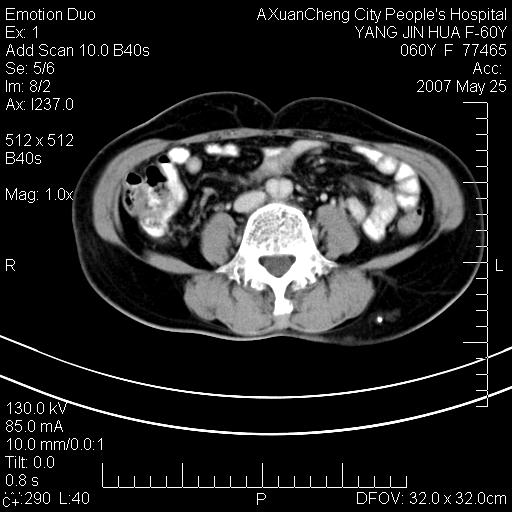

标题: CT8389:背部皮下包块,平扫+增强,急诊请大家看看

发现左侧腰背部包块40余年,逐渐长大,质软,局部表面可见扩张的血管影

左背部皮下良性肿瘤,密度不均,边界不清,内有脂肪、钙化,增强扫描无明显强化,血管平滑肌脂肪瘤?进一步诊断有困难,建议穿刺活检。

左侧背部皮下混杂密度肿块,结构较疏松,边缘欠光整,内有多发斑点状钙化,考虑:皮下血管瘤。

这个病理增强扫描之前,我们是考虑是血管瘤,可是现在增强后一点强化都没有,还能考虑是血管瘤吗